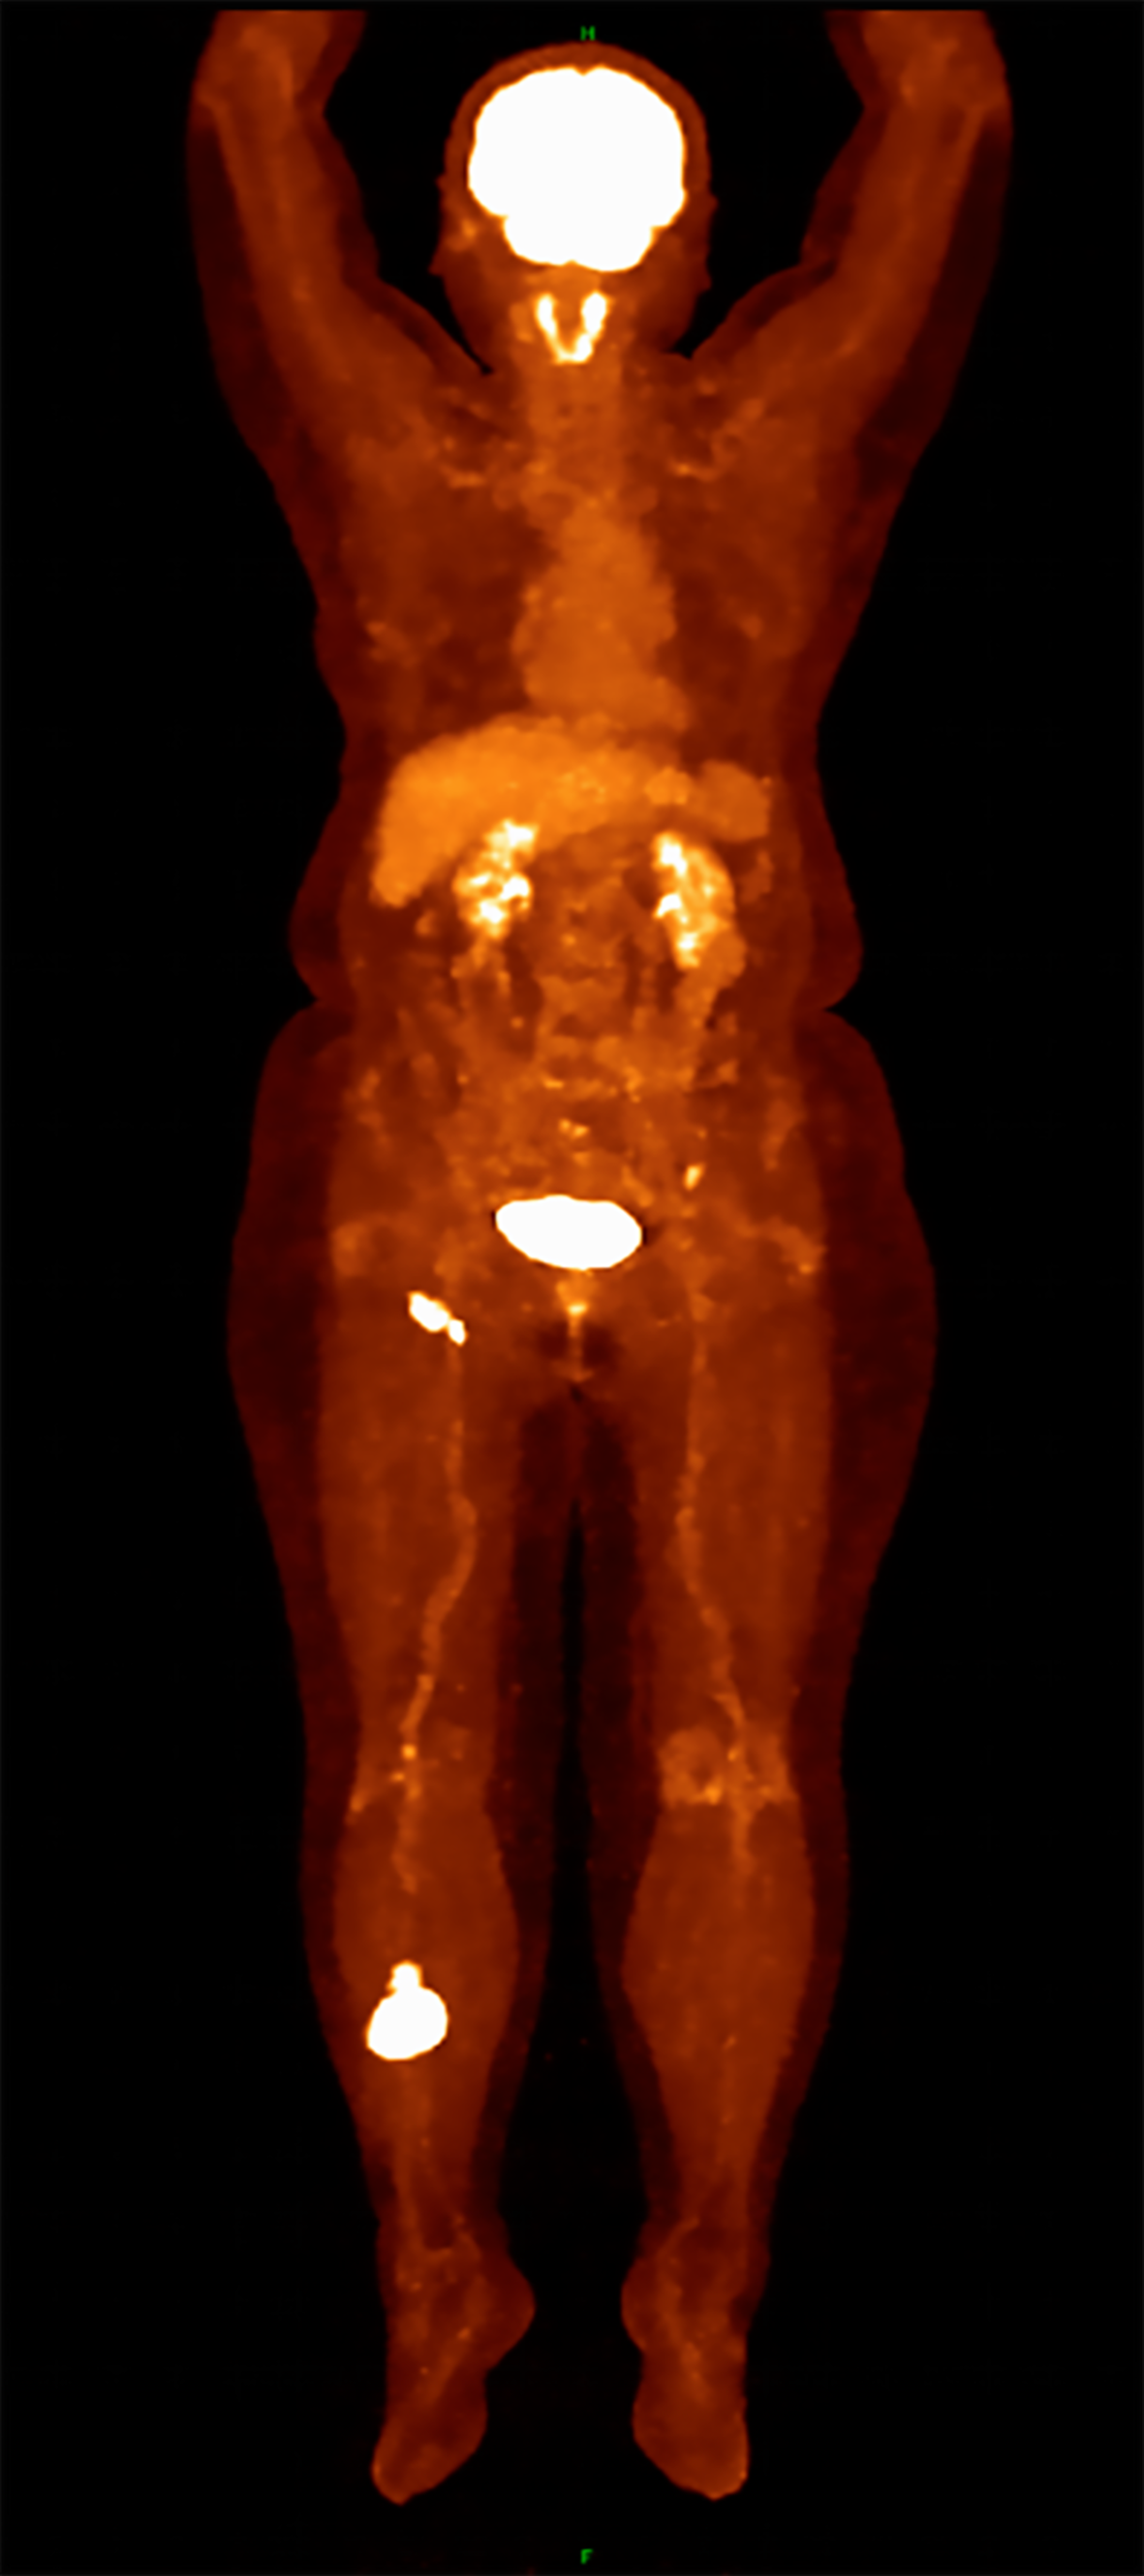

Figure 3 Positron emission tomography-computed tomography imaging findings.

Coronal view demonstrating fluorodeoxyglucose-avid soft tissue mass in the right lower extremity (SUVmax 15.95). Axial view showing multiple hypermetabolic right inguinal lymph nodes (SUVmax 10.54). Both are consistent with lymphomatous involvement.